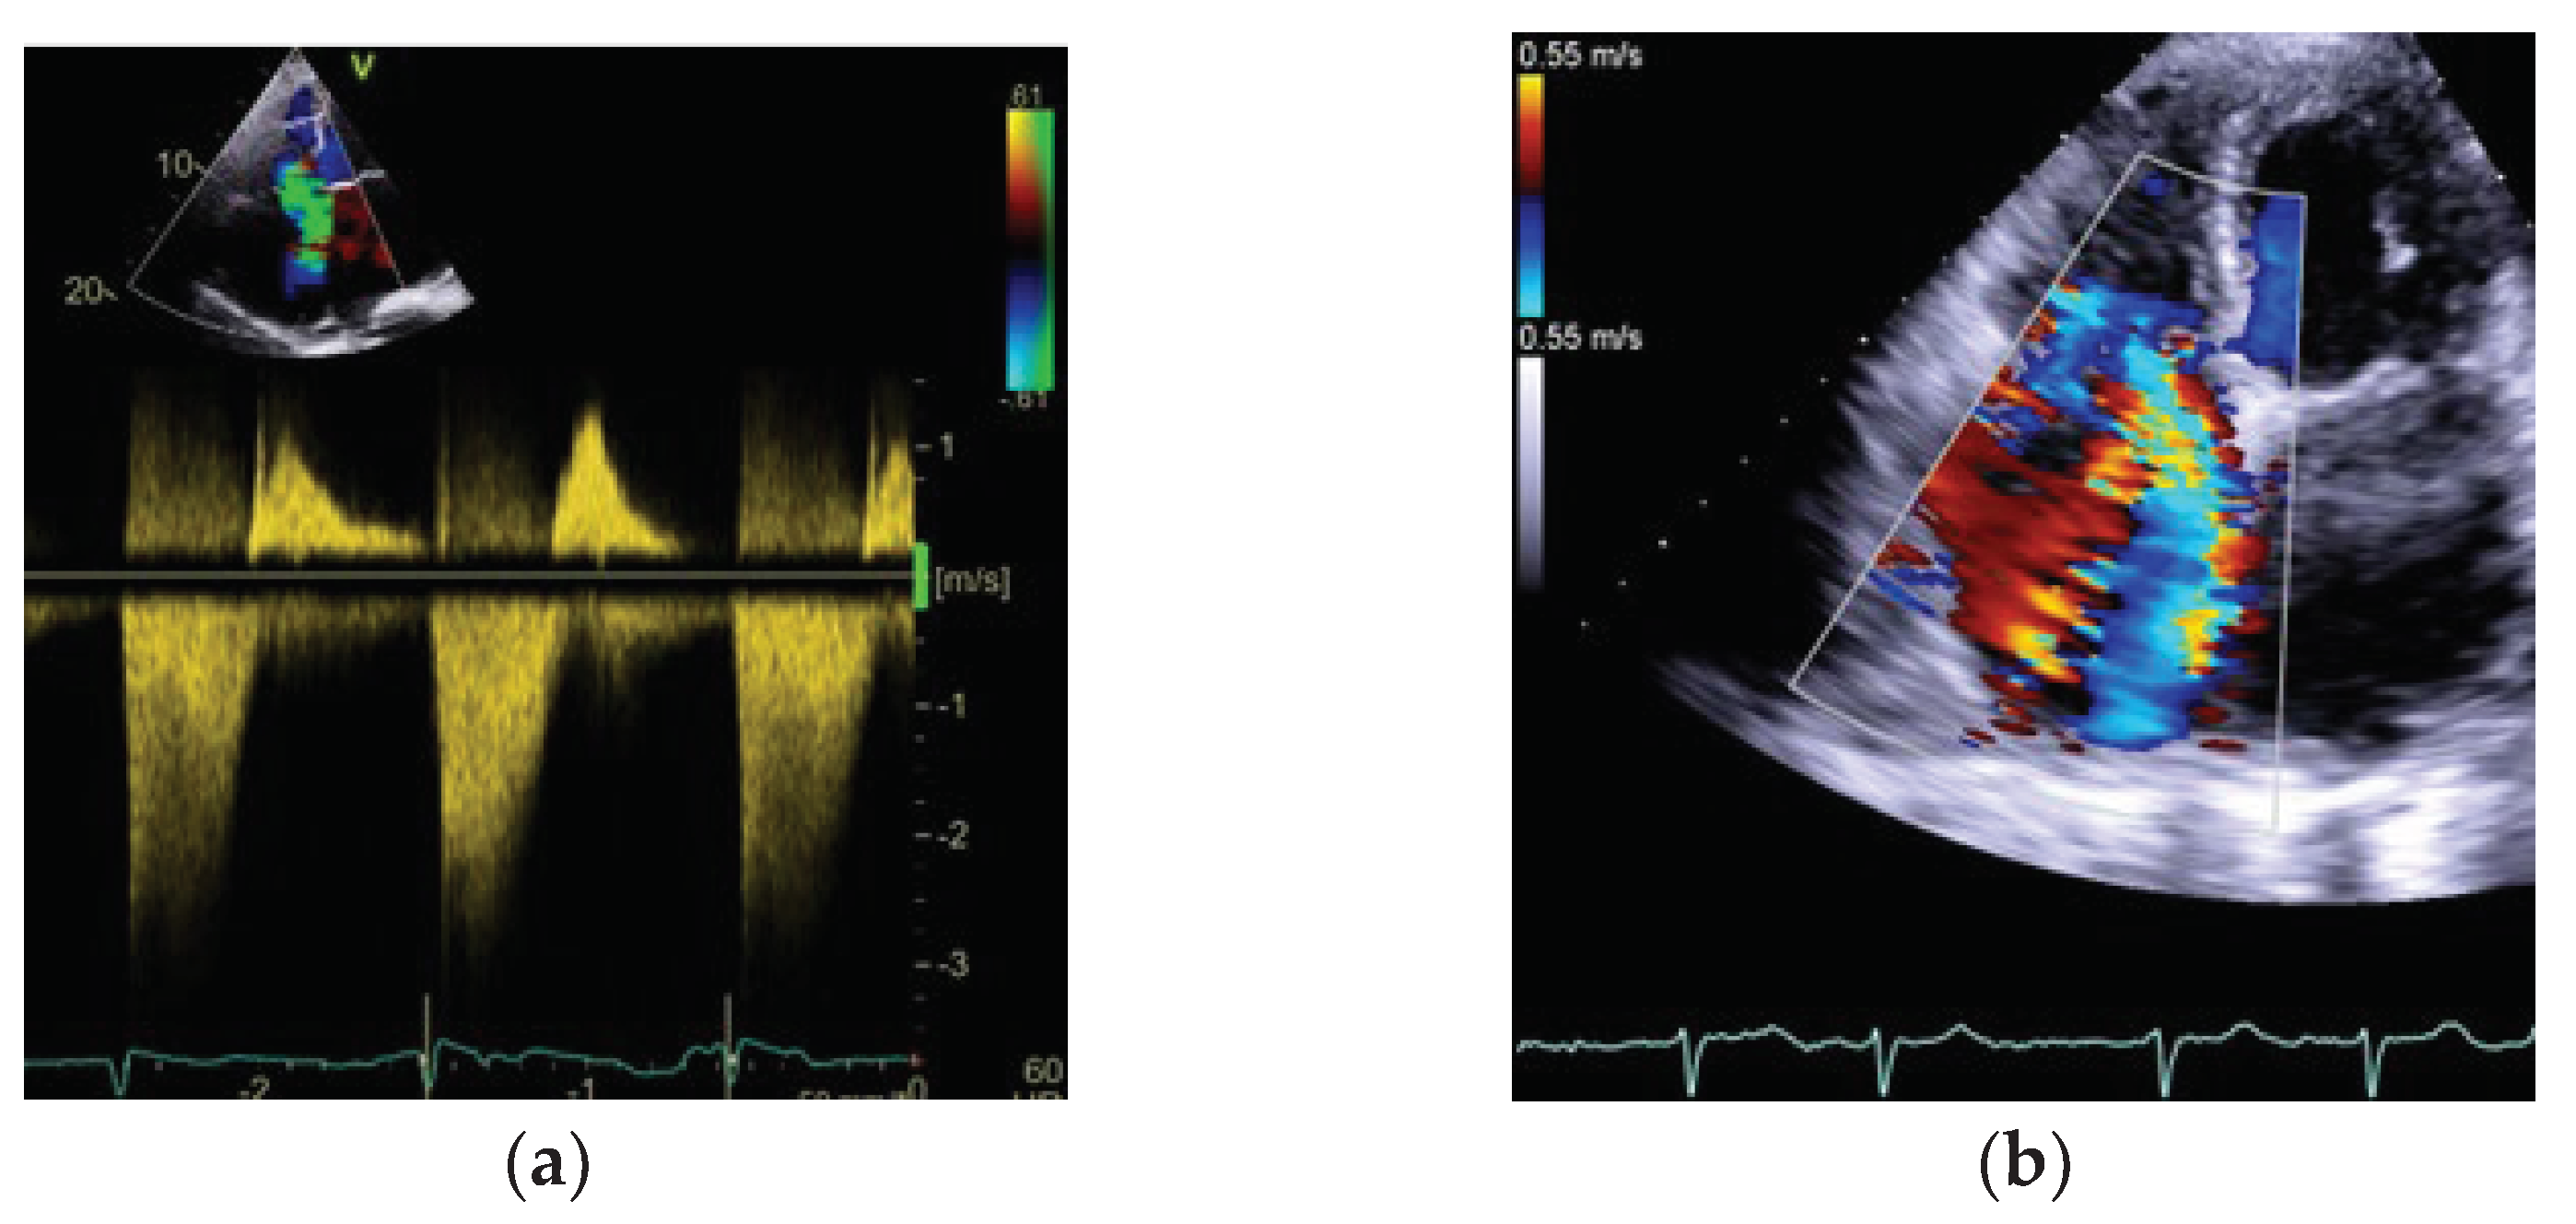

3.2. Tricuspid Regurgitation Velocity Peak (TRVpeak) and PASP Calculation

3.4. Pulmonary Regurgitation

| TRVpeak | PSAX, 4Ch, or any modified view. CW doppler through TV | Proportional -moderate to high | • Severe TR • Assumption of Bernouli equation |

| PASP | PSAX, 4Ch, or any modified view. CW doppler through TV | Moderate | • Severe TR • Assumption of Bernouli equation • Assumption of RAP based on the IVC (size and collapsibility, volume overload situations) – underestimation • Rapid equalization of pressures between RA and RV |

| RVOT-AT | PSAX. May be not well-visualized | High | • Arrhythmias • Impaired RV function in critically ill patients |

| Pulmonary regurgitation | PSAX. May be not well-visualized | Low | • Rare finding |